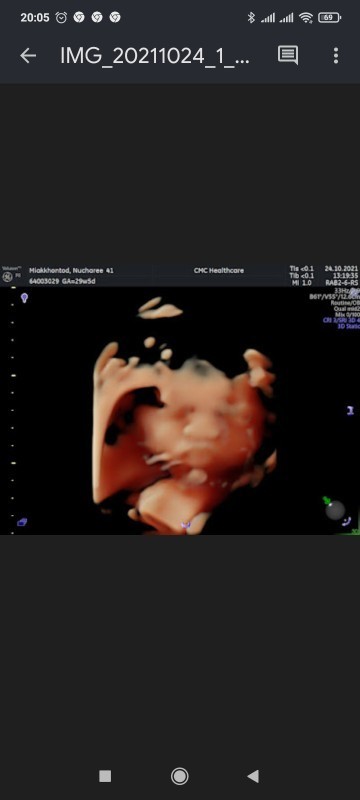

น้อนขี้อายค่ะ...เอามือมาบังหน้า

แม่ช่วยดูหน่อยค่ะว่าญหรือช😂

อยากได้ลูกสาวมากค่ะ 😊 ท้องแรก